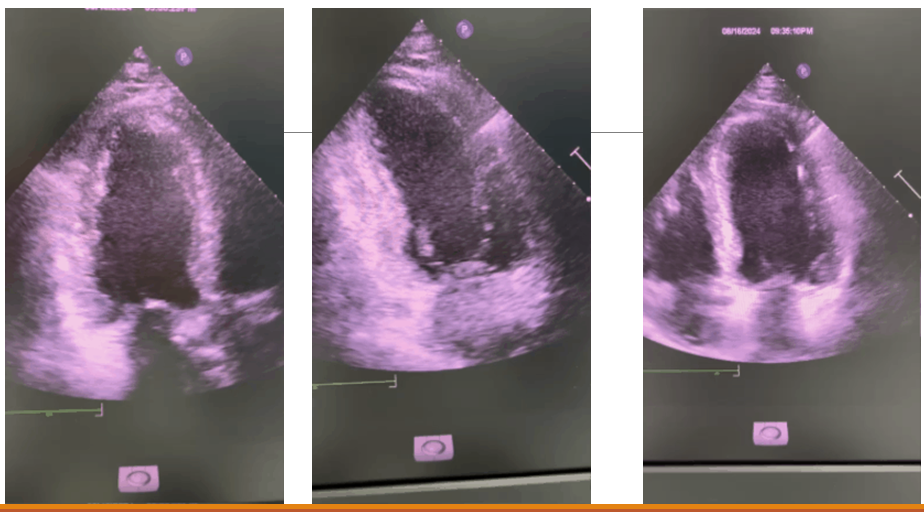

Mặt cắt siêu âm tim

Đánh giá vận động vùng thành tim

- 1 = Bình thường

- 2 = Giảm vận động (< 30% độ dầy tâm thu)

- 3 = Không vận động hay vận động tối thiểu

- 4 = Vận động nghịch thường (thành tim di động ra ngoài trong thì tâm thu)

- 5 = Phình thành tim (mỏng và phình trong cả thì tâm thu và tâm trương)